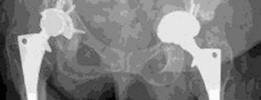

Preoperative Radiological Assessment/Imaging(Figs. 20.9 and 20.10)

Diagnosis : Pelvic discontinuity with severe acetabular bone loss (Paprosky acetabular bone loos classification, IIIb) (Figs. 20.9, 20.10 and 20.11) Possible treatment options : Uncemented reconstruction (acetabular column plating with bulk structural allograft and/or highly porous metal (tantalum) implants with modular augments), ‘cup-cage’ reconstruction, custom (triflange) implants